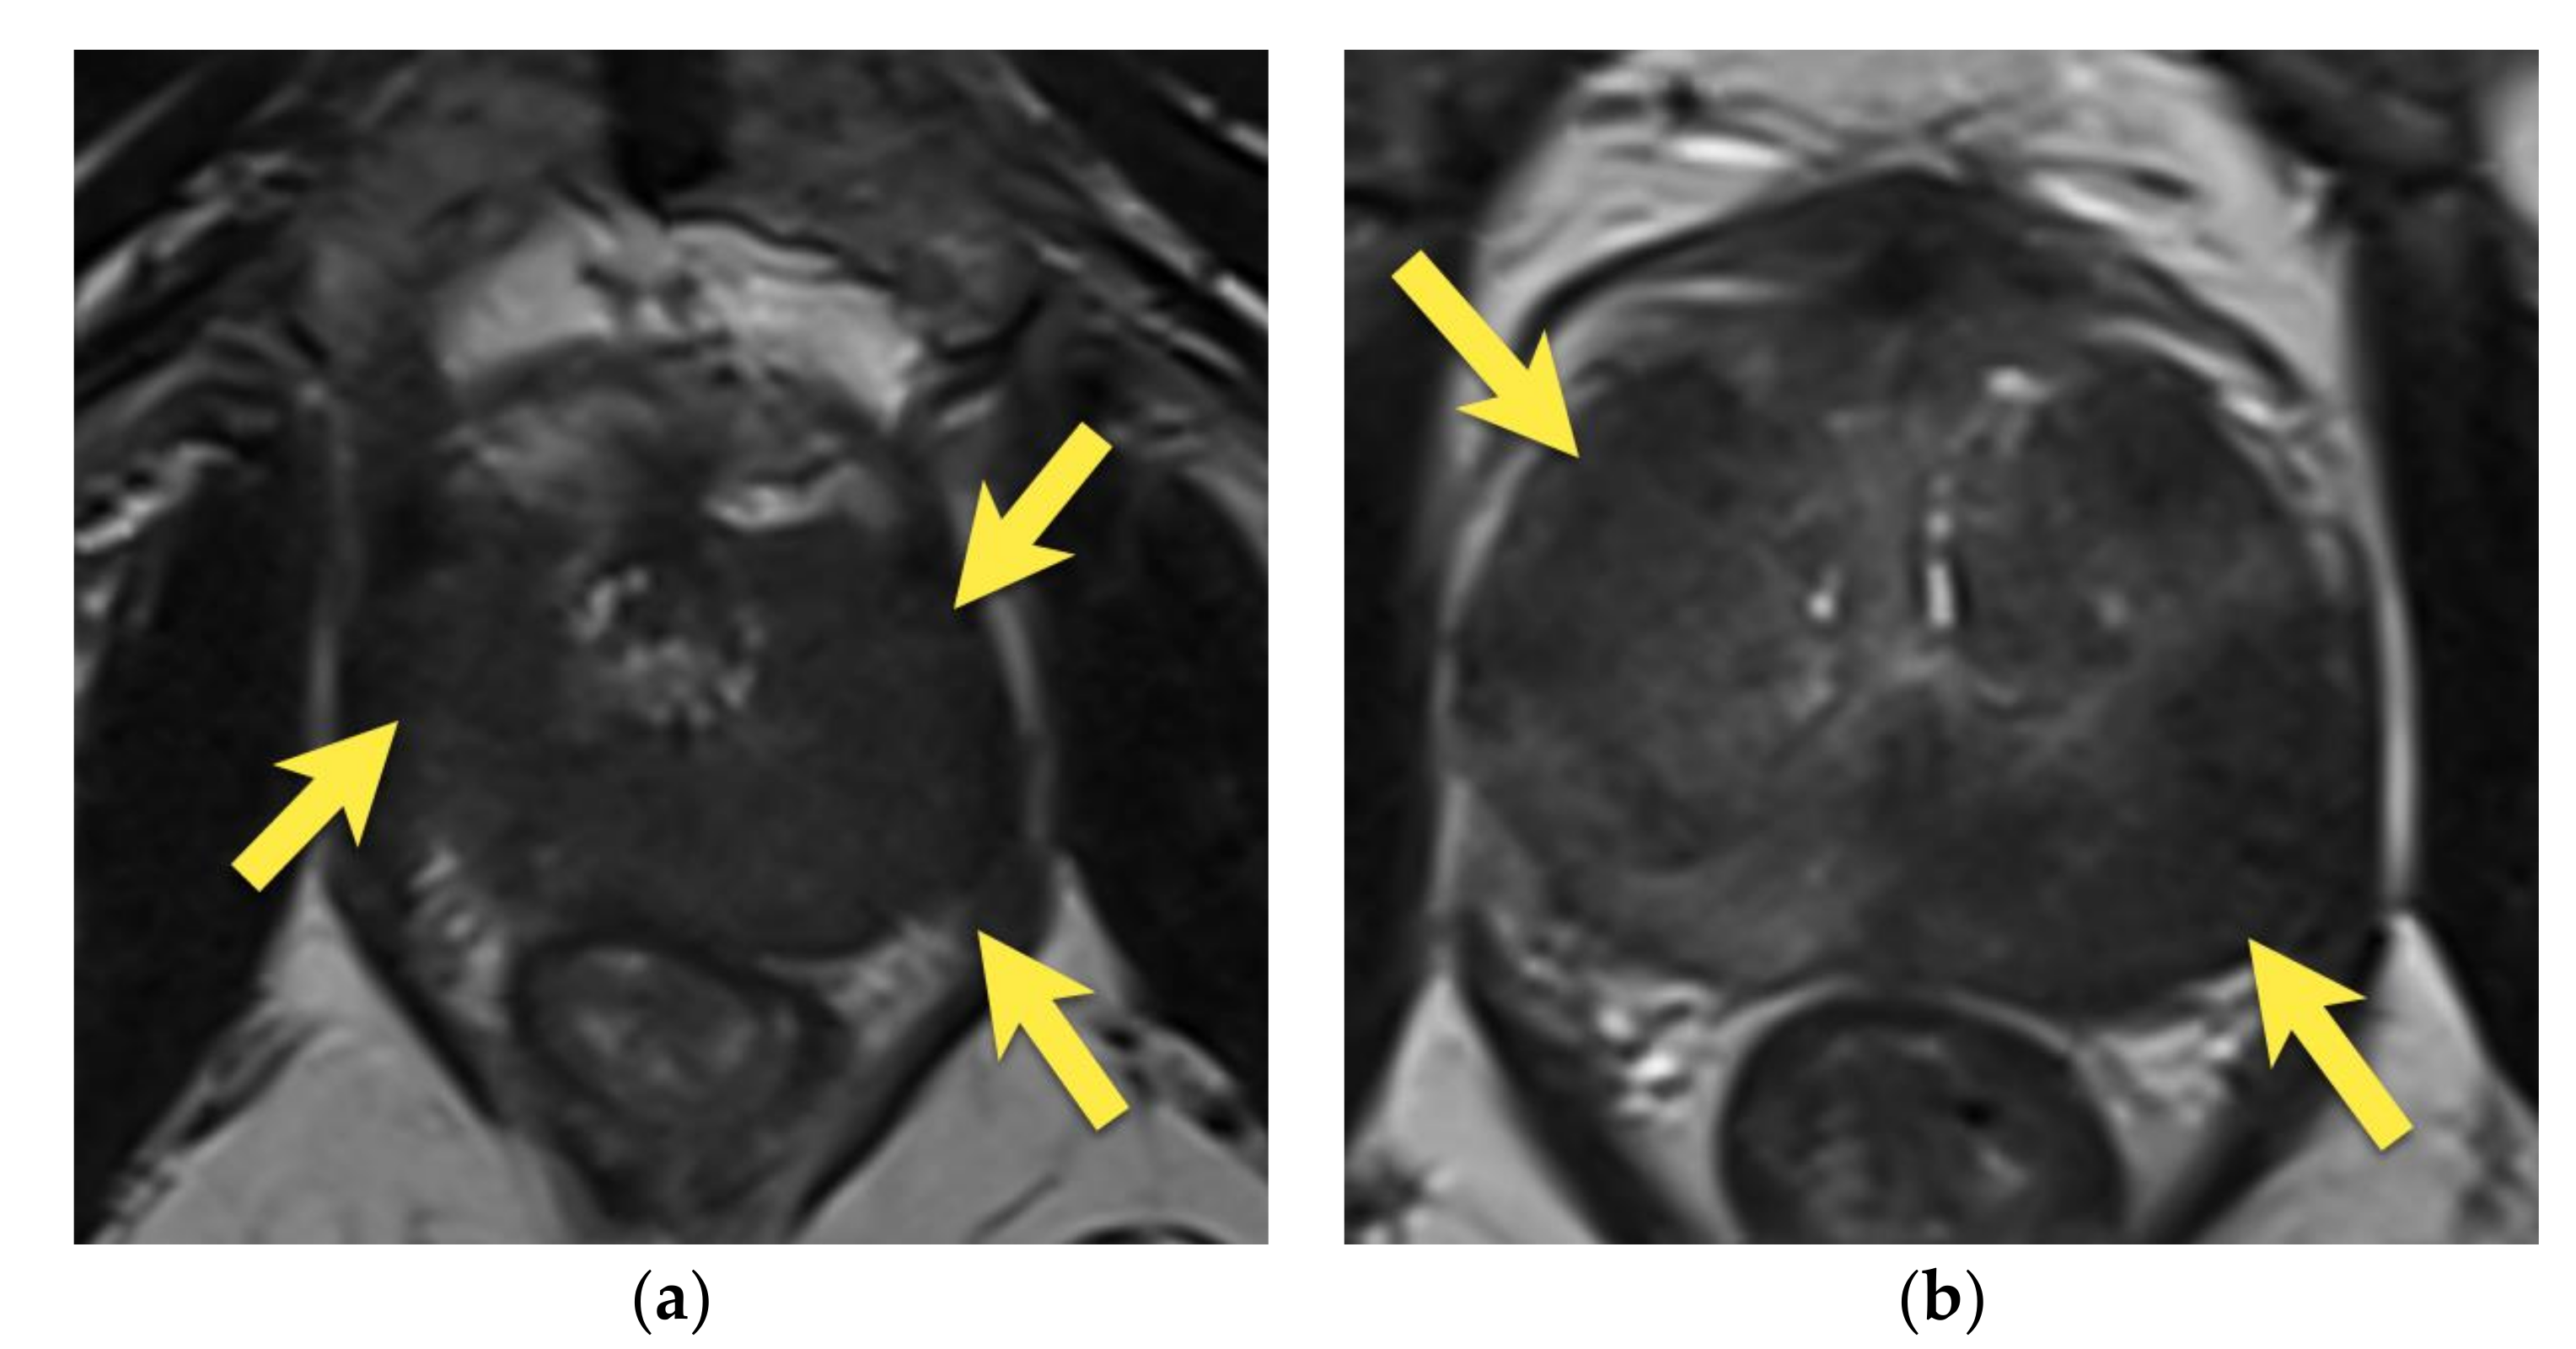

6. Transition Zone—Benign Prostatic Hyperplasia

8. Post-Biopsy Hemorrhage

9. Prostatitis